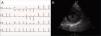

Case reportA 19-year-old woman presented palpitations and chest discomfort, unrelated to exertion and with no pleuritic characteristics, without reports of syncope, during the previous year. She had no relevant medical history and no known relevant family history of cardiac, renal, neurologic or genetic diseases; she was not under any medication and did not practice any sports. Her family physician performed a physical exam that was unremarkable (including blood pressure), except for an arrhythmia on cardiac auscultation. He requested an electrocardiogram (Figure 1A) which revealed sinus arrhythmia, biphasic T waves in leads DII, aVF and V3, and T-wave inversion in leads DIII and V4–V6. On the basis of this abnormal ECG clinical observation by a cardiologist was requested, in which the patient underwent more diagnostic exams. The echocardiogram revealed no significant abnormalities, except the presence of hypertrophic PMs (Figure 1B); LV mass was normal and maximum ventricular wall thickness was 11 mm at the interventricular septum in parasternal long-axis view. There were no significant valvular abnormalities. Despite the presence of prominent PMs, no significant intraventricular gradient or LV outflow tract obstruction was found on Doppler evaluation at rest. For further clarification and to assist with differential diagnosis, CMR imaging was performed. This exam showed a normal right ventricle and normal valve structures. The left ventricle had normal systolic function (60% ejection fraction), with a mass of 59 grams (35.5 g/m2), end-systolic volume of 42 ml and end-diastolic volume of 104 ml. Maximum ventricular wall thickness was 11.2 mm at the interventricular septum measured in end-diastole, 4-chamber view. Both PMs were also seen to be abnormally hypertrophic (Figures 2 and 3), occupying a large part of the LV cavity during systole (Figures 2A and 3A). The anterolateral PM had a maximum diameter of 12.5 mm and the posteromedial PM measured 15 mm on the horizontal axis (end-diastole, short-axis view; Figure 3B). Delayed hyperenhancement was not observed.

(A) 12-lead electrocardiogram showing the repolarization abnormalities described in the text. The voltage sum of the S wave in V1 and the R wave in V5 is 36 mm, but this patient was 19 years old, so the voltage criterion for left ventricular hypertrophy of ≥35 mm is not applicable; (B) echocardiographic image at the level of the papillary muscles (short-axis view at end-systole).